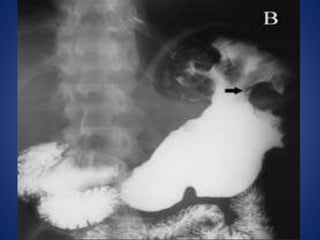

IMÁGENES CLASICAS DIAGNOSTICAS EN

EL 20%

Pruebas diagnosticas • Ecografía •Tomografía axial computarizada • Resonancia magnética nuclear • Lavado peritoneal diagnóstico • Laparoscopia • Radiografía de tórax • Placas simples de abdomen

IMÁGENES CLASICAS DIAGNOSTICASEN EL 20% SENSIBILIDAD 10%